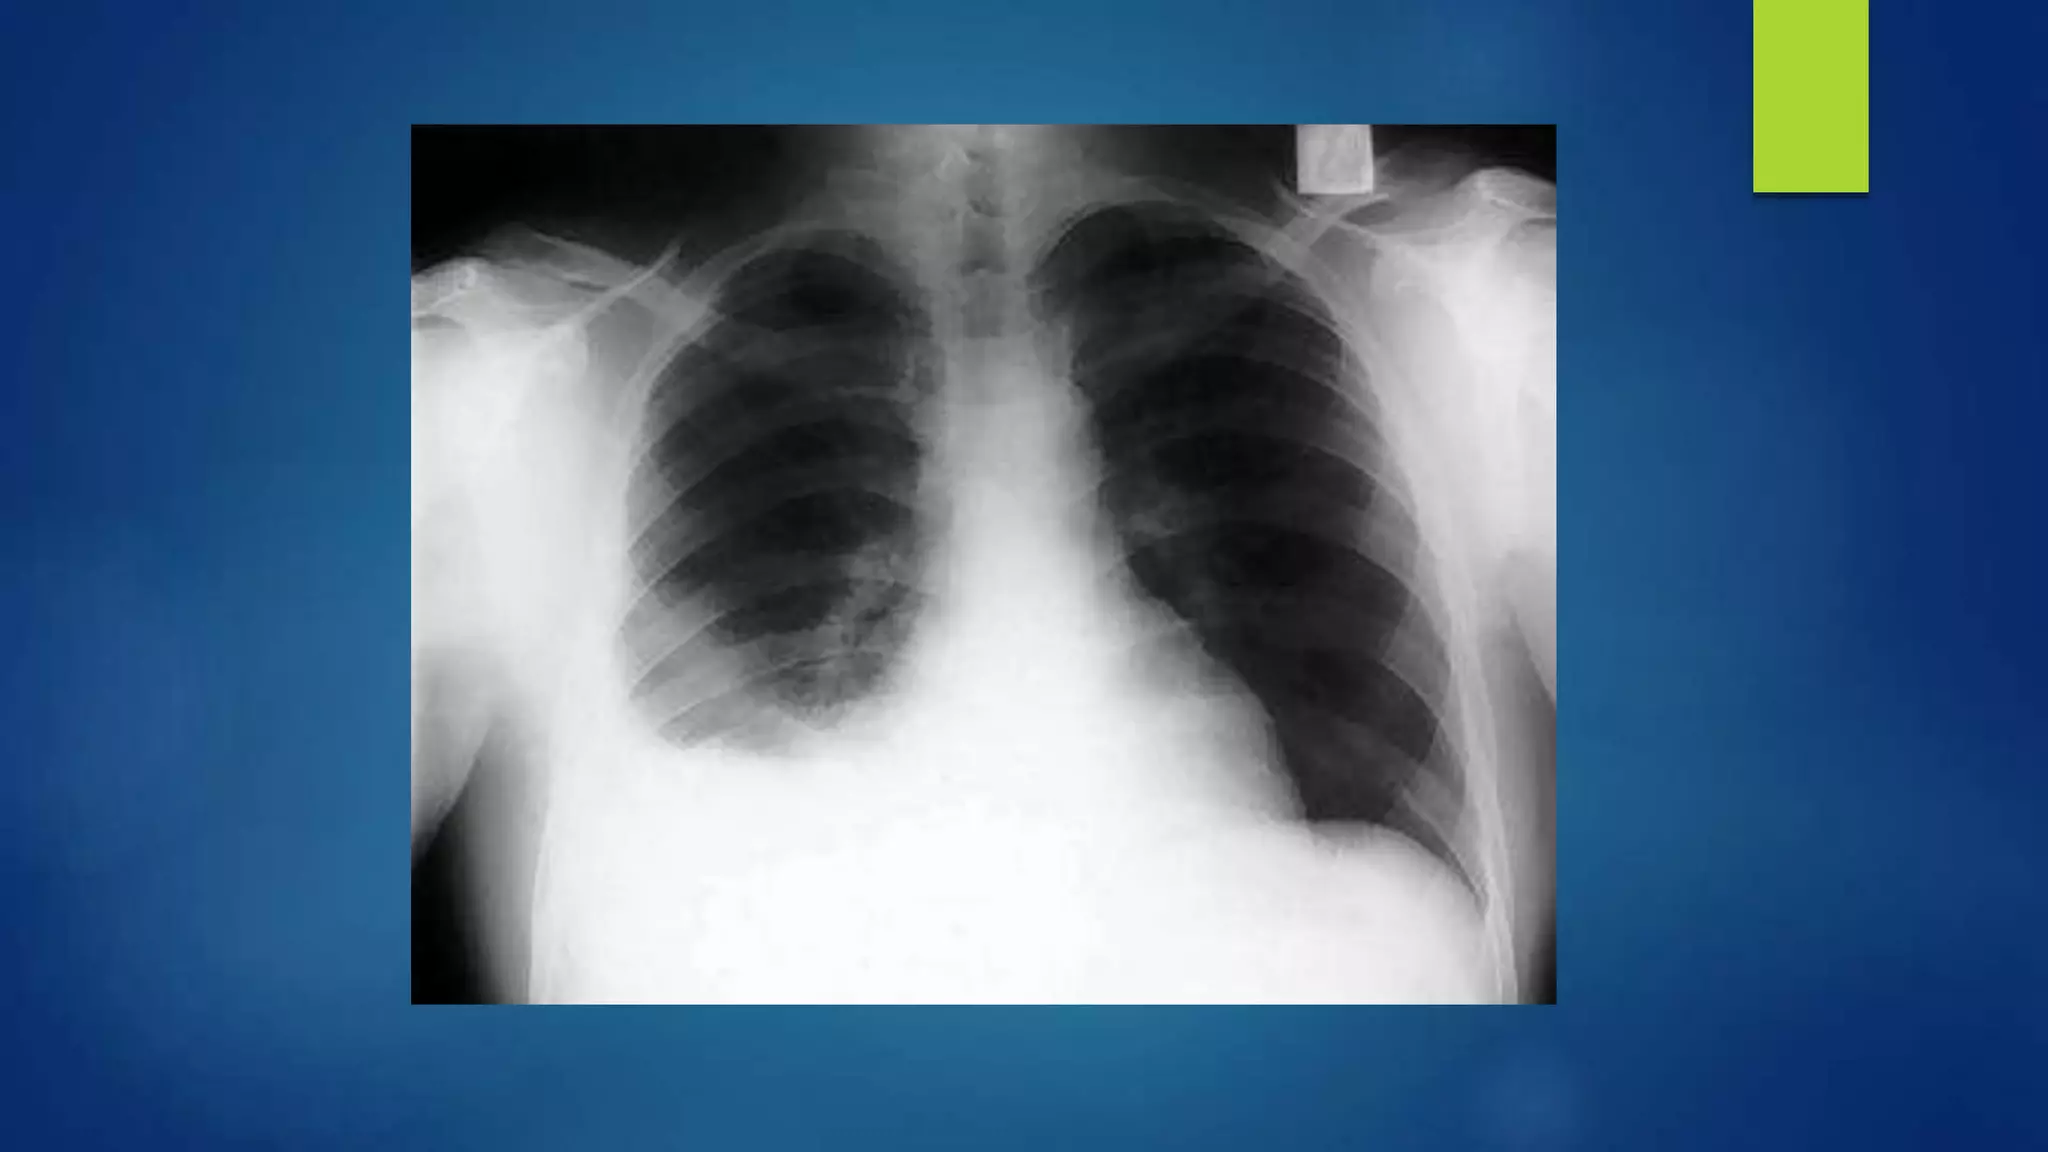

Imaging studies:

 Radiologic evaluation is the primary tool for the diagnosis of a parapneumonic effusion

 Frontal, decubitus and lateral radiographs

 Chest radiograph : Obliteration of CP angle is the earliest sign of an effusion and a rim of

fluid may be seen ascending the lateral chest wall (meniscus sign).

 A lateral decubitus film is the most sensitive view and can detect as little as 5-10 mL of free

fluid.

 A fluid layer of more than 1 cm on decubitus film is amenable to thoracentesis.

 Non-shifting fluid suggests either thick fluid or loculation.